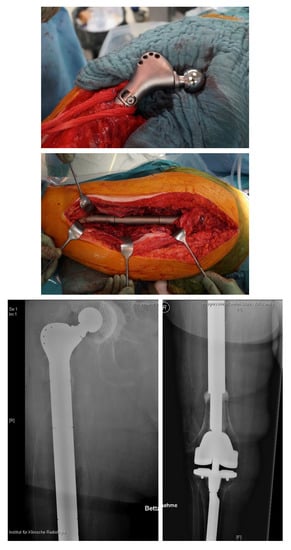

The “Osteobridge®” is a modular system which spans the fracture according to the distal and proximal end, respectively, over the implant stems of the endoprosthesis [29]. Interposition devices, such as the “RescueSleeve®”, are used to replace the fractured diaphyseal bone and to couple both ends of the hip and knee stem using two screws connecting the sleeves (Figure 5) [30], while custom-made sleeves could be used to couple a stable implant to a tumor endoprosthesis (AQ-Implants GmbH, Ahrensburg, Germany) (Figure 6).

Figure 5.

Custom-made interposition sleeve (Waldemar Link GmbH, Hamburg, Germany).

Figure 6.

Interprosthetic fracture around a stable total knee revision arthroplasty and a loose total hip revision arthroplasty. Implantation of a custom-made docking sleeve coupled to a proximal femur replacement (AQ-Implants GmbH, Ahrensburg, Germany).